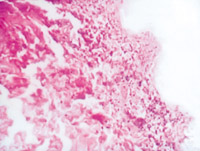

5-2-3 傷后第3天,表皮細胞空泡化,真皮淺層膠原纖維玻璃樣變,真皮內(nèi)散在炎細胞浸潤  HE×100